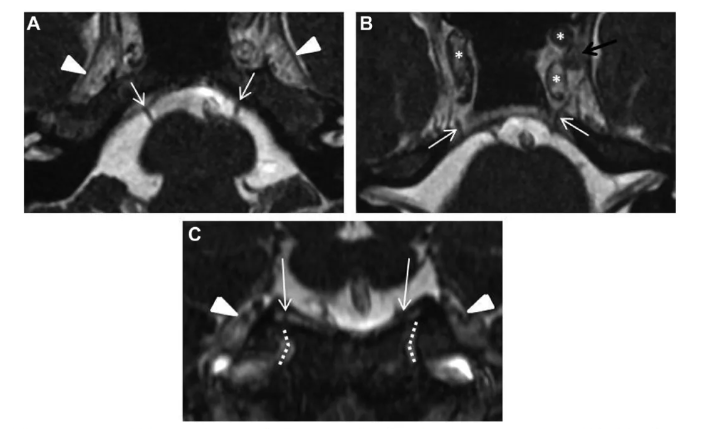

增强 MRI 显示病灶在岩尖、耳蜗和内听道侧面和后部出现均匀强化病灶, T2 低信号和 T1 高信号,病灶导致右侧内听道 ICA 和海绵窦向前移位。

选择从左侧鼻孔内部进入(对侧单鼻孔入路),这样能更安全地到达位于右侧岩尖的目标囊肿。

手术中,左侧鼻中隔皮瓣切开并进行蝶窦切开术,以到达岩尖区域。